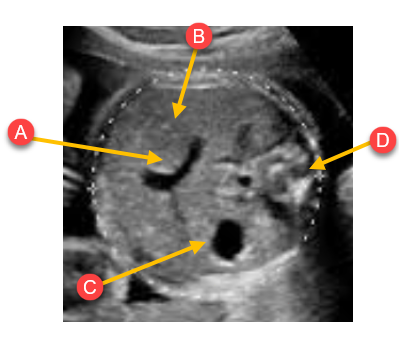

Label the anatomy with the arrows

A. Umb. vein

B. Liver

C. Stomach

D. Spine